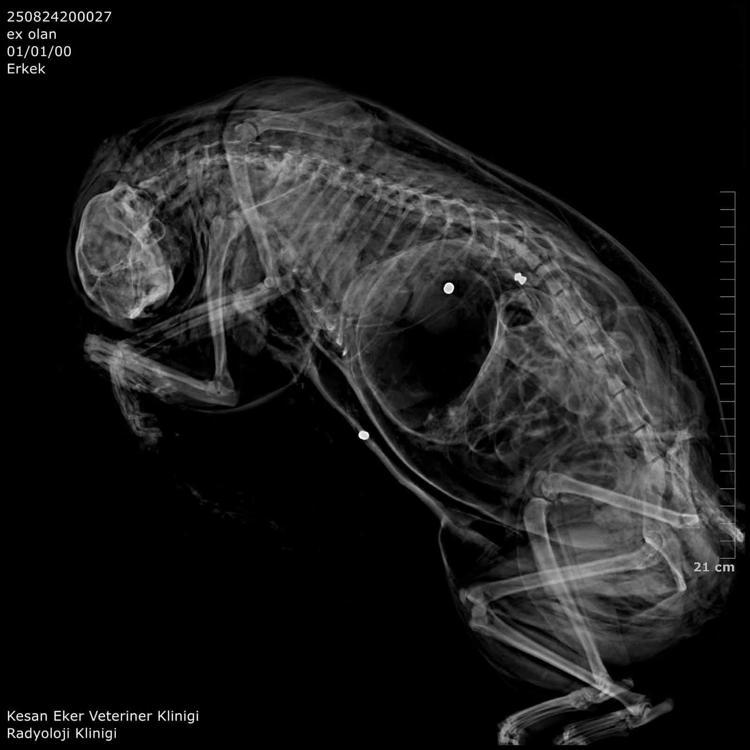

İpsala Cumhuriyet Başsavcılığı'nın olaya ilişkin hazırladığı iddianamede K.G., hakkında, 'Bir ev hayvanını veya evcil hayvanı kasten öldürme' suçundan 6 aydan 3 yıla kadar hapis cezası istendi. İddianamede, "Herhangi bir silah ateşleme görüntüsü tespit edilmese de şüphelinin ikamet ettiği evin bahçe kapısı önünde bir kedinin can çekiştiği ve bir kedinin de kaçtığının tespit edildiği, dosya kapsamında tanık olarak beyanı alınan S.Ç.'nin şüphelinin bahçe kapısı önünde bir kediyi yatar vaziyette gördüğünü, başını sevmek istediğinde kedinin ölü olduğunu fark ettiğini, kediyi eline aldığında başından kan aktığını görmesi üzerine yol üzerinde kalmaması amacıyla kediyi çöp tenekesinin içerisine bıraktığını, ölen ve yaralanan 2 kedi hakkında düzenlenen 25/08/2025 tarihli veteriner hekim ön muayene raporu ile çekilen radyografilerde ateşli silah yaralanması (kuş saçması) ile uyumlu patolojiler gözlemlendiği şeklinde rapor tanzim edildi.

Tüm dosya kapsamı incelenmekle şüpheli savunması, bilgi sahibi beyanları, İpsala İlçe Tarım Müdürlüğü'nün yazılı başvurusu, müşteki beyanı, kamera görüntüleri ve kriminal raporları birlikte değerlendirildiğinde, şüphelinin olay tarihinde müşteki Hüseyin Bülbül tarafından da beslenmekte olan sokak kedilerine ateş etmek suretiyle, bir kedinin ölümüne neden olarak üzerine atılı suçu işlediğine dair ve bir kedinin yaralanmasına neden olarak tariflenen suçu işlediğine dair hakkında kamu davası açmak üzere yeterli şüphe oluşturacak kadar delilin mevcut olduğu anlaşılmakla" denildi.